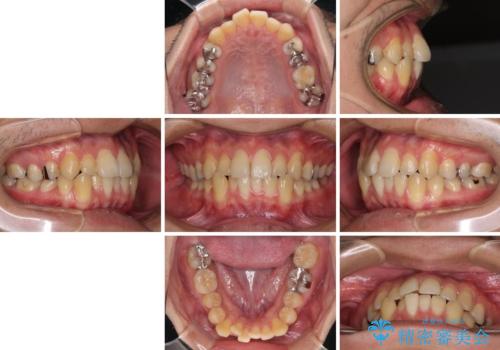

前歯のクロスバイトをインビザラインで矯正治療

- 前歯のデコボコとクロスバイトを気にして来院された患者様です。

前歯を早く整えたいとの希望があったので、ワイヤー矯正にて短期間でクロスバイトを解消し、その後インビザラインにて整えることとしました。

インビザラインによる前歯のクロスバイト改善におけるリスクとして、前歯歯髄充血・歯髄壊死が挙げられます。

ワイヤー矯正を併用する目的として、短期間でデコボコやクロスバイトを改善する他に、歯髄充血リスクを低減させるというものがあります。